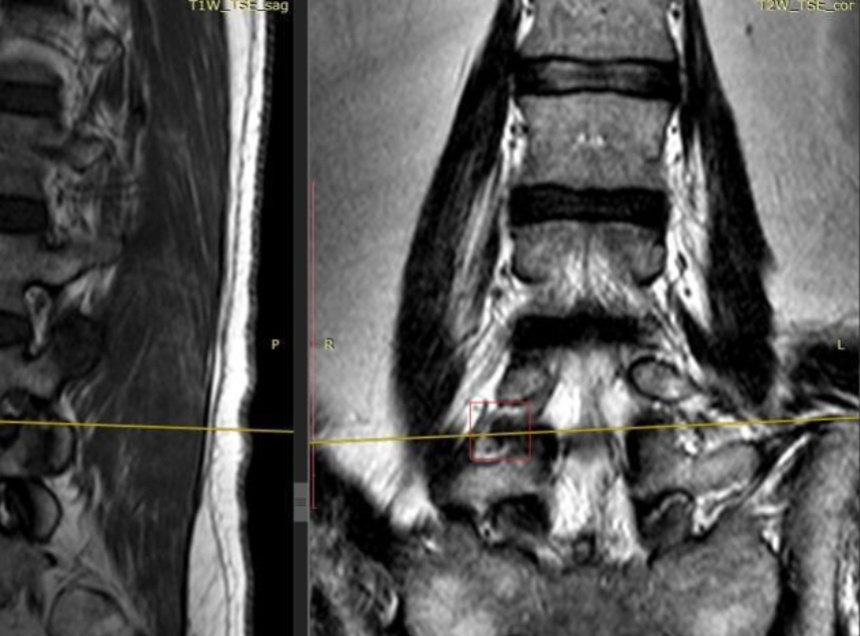

Затруднения в осмотре пациента вызывал выраженный болевой синдром. МРТ показала, что у мужчины экстрафораминальная грыжа межпозвонкового диска между 4 и 5 поясничными позвонками справа с грубой компрессией спинального корешка.